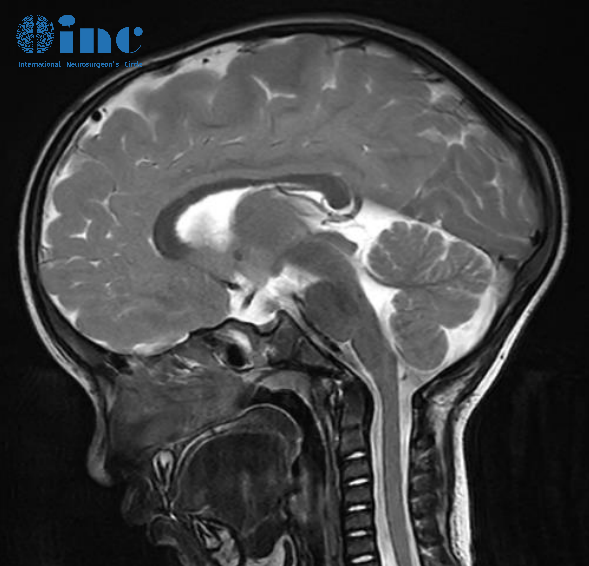

三维重建的CT扫描和MRI:

CT扫描显示,矢状缝的早闭使颅骨增大受限,同时导致了前颅窝和后颅窝的代偿性增长。也有适度的垂直增长。鳞状缝也闭合,但顶骨的上部有代偿性的过度生长。

然而,脑室系统是正常的。这些发现被MRI检查所证实。

检查排除了小脑扁桃体尾端疝。这是矢状缝早闭诱发因素发展并伴有脑积水的一种不同亚型的特征。

总之,神经影像学研究证实了矢状缝早闭的临床诊断,但在这个特定的孩子中应该被认为是中度。检查排除了异常的脑脊液动力学,以及由于颅骨侧向生长受限而导致的脑实质受损区域。额部和枕部隆起是未经治疗的矢状缝早闭的自然代偿。